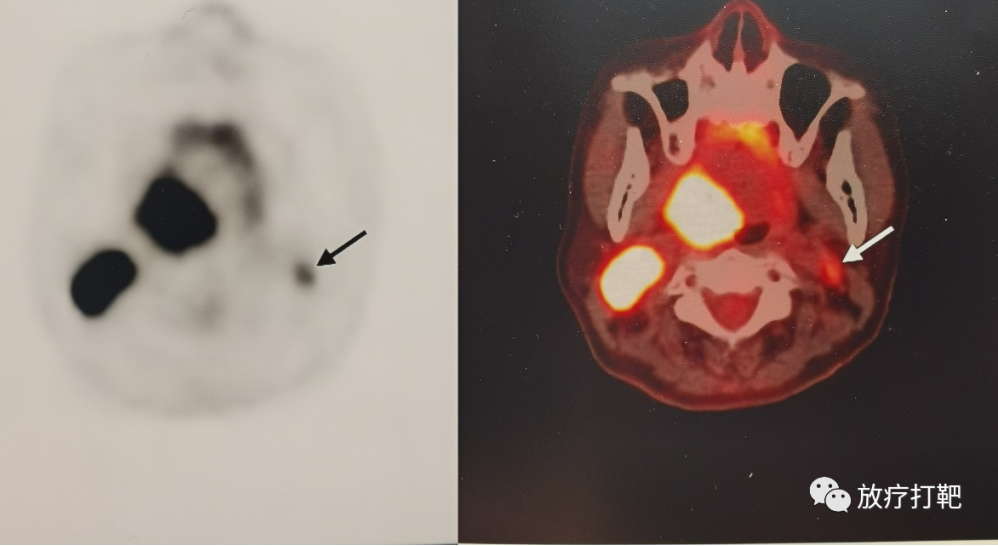

扁桃体癌颈部淋巴结转移不用手术未毁容貌通过放化疗彻底清除

图片尺寸998x546